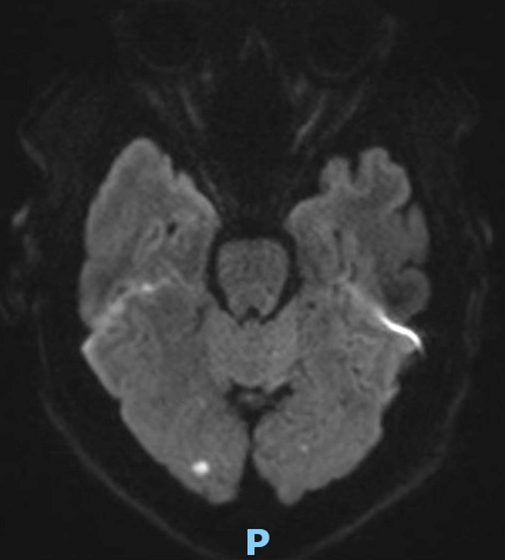

Le type d’hémianopsie est très important car il permet de localiser une atteinte neurologique, en connaissant le trajet des voies optiques.

Figure d’après le Collège des enseignants de neurologie (CEN). Altération aiguë de la vision.

Cette question supposait d’avoir bien en tête le schéma des voies optiques, et d’avoir des repères sur les principaux territoires vasculaires cérébraux et l’atteinte clinique associée. Il bien mentionné par le CEN que l’hémianopsie latérale homonyme gauche peut se voir dans un AVC sylvien superficiel droit.